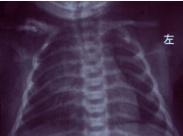

鎖骨骨折是產(chǎn)傷性骨折中最常見的一種,與分娩方式、胎兒娩出方式位和出生體重有關(guān)。難產(chǎn)、胎兒轉(zhuǎn)位幅度大、巨大兒發(fā)生率高。

新生兒產(chǎn)傷是指分娩過程中因機(jī)械因素對(duì)胎兒或新生兒造成的損傷。近年來由于加強(qiáng)了產(chǎn)前檢查及產(chǎn)科技術(shù)提高,產(chǎn)傷發(fā)生率已明顯下降,但仍是引起新生兒死亡及遠(yuǎn)期致殘?jiān)蛑唬绕涫窃诨鶎訂挝弧fi骨骨折是產(chǎn)傷性骨折中最常見的一種,與分娩方式、胎兒娩出方位及出生體重有關(guān)。